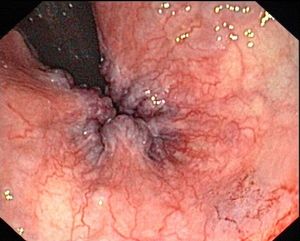

치핵은 일반적으로 신체 검사를 통해 진단된다.[6] 항문과 주변 부위를 육안으로 검사하여 외치핵 또는 탈출 치핵을 진단할 수 있다.[2] 반면 내치핵의 육안 확인에는 한쪽 끝에 조명이 부착된 속이 빈 튜브 장치인 항문경 검사가 필요할 수 있다.[8] 직장 수지 검사 (DRE)를 통해 직장 종양, 폴립, 비대해진 전립선, 또는 농양의 존재 여부를 확인할 수도 있다.[2] 통증으로 인해 적절한 진정 없이 이 검사를 수행하기 어려울 수 있지만, 대부분의 내치핵은 통증과 관련이 없다.[7] 통증이 있는 경우 내치핵보다는 치열이나 외치핵일 가능성이 더 높다.[8]

5. 1. 신체 검사

항문 및 주변 부위를 육안으로 검사하여 외치핵 또는 탈출된 치핵을 진단할 수 있다.[2] 직장 수지 검사 (DRE)를 통해 직장 종양, 폴립, 비대해진 전립선, 또는 농양의 존재 여부를 확인할 수도 있다.[2] 대부분의 내치핵은 통증과 관련이 없지만,[7] 통증이 있는 경우 내치핵보다는 치열이나 외치핵일 가능성이 더 높다.[8] 한쪽 끝에 조명이 부착된 속이 빈 튜브 장치인 항문경 검사가 내치핵의 육안 확인에 필요할 수 있다.[8]| 단계 | 도해 | 그림 |